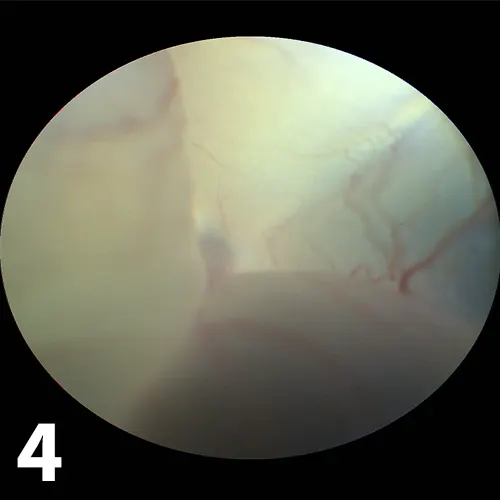

• Signs of optic disc inflammation (eg, edema, congestion, focal hemorrhage, disc elevation, peripapillary retinal detachment) may be seen in cases of proximal optic neuritis. A common sequela is optic atrophy, in which patients present with a round brown-gray disc (Figure 3). These patients should undergo neurological evaluation.4,5

• A detached retina can be seen as a vascular, white-gray veil behind the lens (Figure 4). Varying degrees of intra- or subretinal hemorrhage may be seen. When the fundus cannot be seen (eg, because of severe corneal edema or hyphema), the detachment may be demonstrated by ultrasound. Rhegmatogenous retinal detachments, in which liquified vitreous enters the subretinal space through a retinal hole, are usually primary. No detailed evaluation is required, and patients can be referred to a specialist for retinal reattachment surgery if indicated. Other types of retinal detachments may be caused by systemic hypertension, systemic infections, or vascular diseases. These require a full systemic evaluation. Successful treatment of the primary cause may cause retinal reattachment and restored vision.6,7